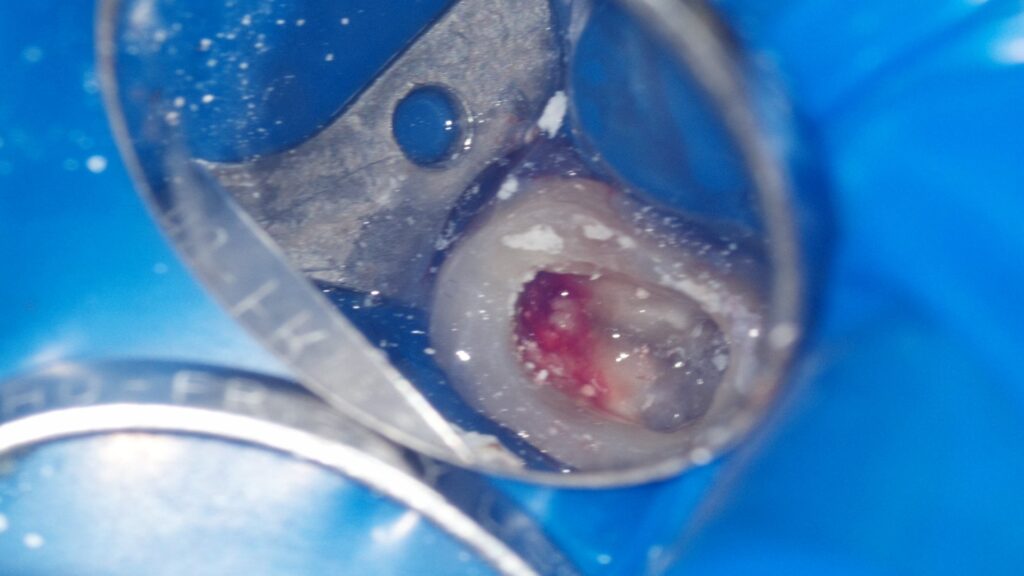

実際の治療中のマイクロスコープで確認した画像です。

奥歯の場合、いくつかの根管に分かれているため、すべての根管を丁寧に清掃していきます。

マイクロスコープを用いて高倍率で確認すると、1本の根管と思われていた部分が、途中から枝分かれして2本となっていました。

根管の形は全ての歯で異なっており、一つとして同じものは存在しません。CT画像と実際のマイクロスコープの画像を重ね合わせることで、全ての根管を清掃し、治療の成功率を上げることが可能となります。